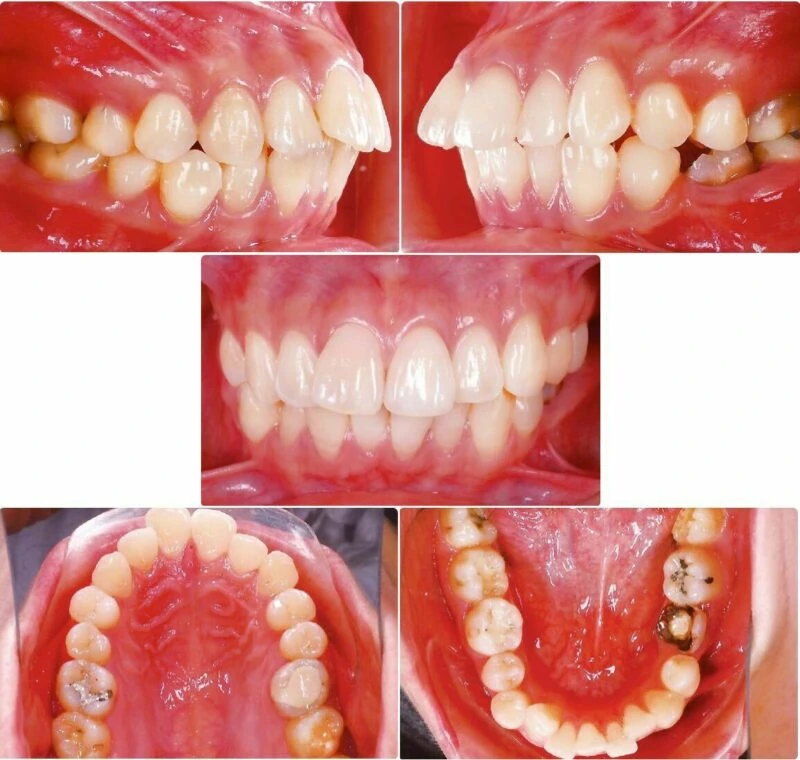

Bệnh nhân nữ trẻ, 24 tuổi được gia đình chuyển đến nha sĩ để tham khảo ý kiến (Hình 1) với lý do bị vẩu, các răng trước và rìa cắn các răng cửa dưới không đều (Hình 2-3). Bệnh nhân mong muốn giải quyết mà không phẫu thuật chỉnh hàm hoặc sử dụng minivis. Không có bệnh lý y khoa kèm theo nhưng bệnh nhân có tiền sử mất răng hàm nhỏ thứ hai ở hàm dưới bên trái và điều trị tuỷ không tốt ở cả hai răng hàm lớn thứ nhất bên trái. Khám lâm sàng ghi được tương quan răng hàm loại I bên phải, nhưng bên trái là loại III. Đường giữa răng hàm dưới lệch sang trái 2mm so với đường giữa mặt và hàm trên. Các răng cửa bên hàm trên bị lệch về phía khẩu cái cả hai bên.

Hình 2 Ảnh chụp trong miệng trước điều trị